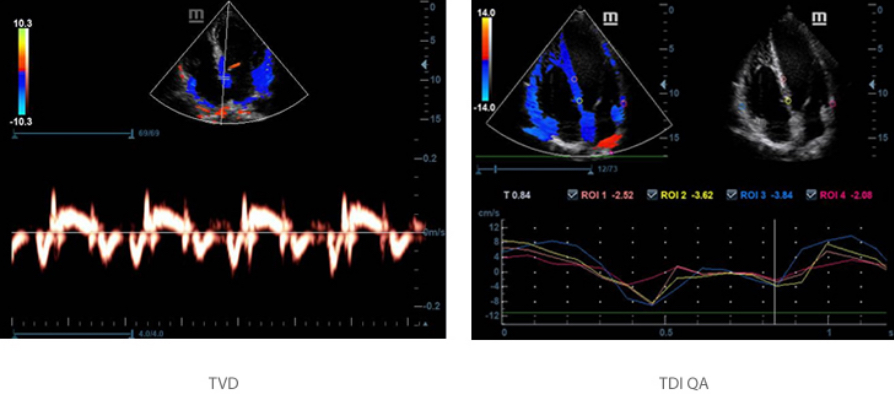

TDI y TDI QA

La herramienta de diagnĂłstico por imĂĄgenes Doppler tisulares (Tissue Doppler Imaging, TDI) le permite evaluar cuantitativamente el movimiento y la funciĂłn del miocardio mediante un parĂĄmetro de velocidad cuantitativo en TDI?QA.

Free Xros CM?

EvalĂșe con precisiĂłn el movimiento del miocardio en diferentes fases y, simultĂĄneamente, determine su sincronizaciĂłn. Alta velocidad de cuadros que ofrece resultados precisos.